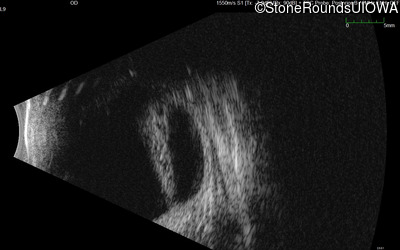

B-Scan Ultrasonography - Right - 20/600

Exemplar

B-Scan Ultrasonography - Left - 20/300